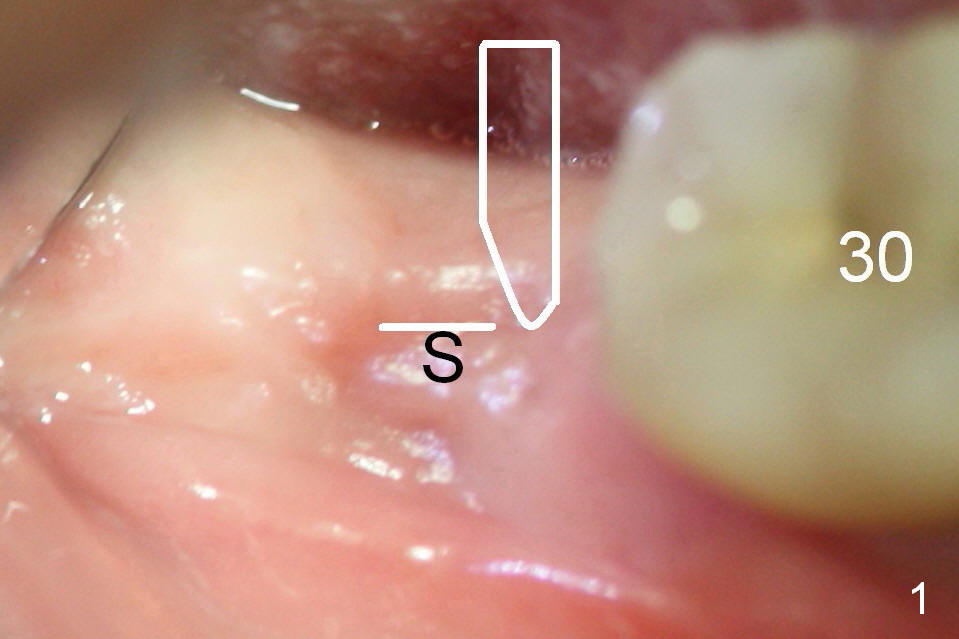

Steps of Bone Expansion (Illustration)

After incision and flap elevation, use #15 blade (Fig.1 white outline) to start bone expansion as lingual as possible (white line). Use bone scalpels, bone blades and D osteotomes to push the bone buccally (Fig.2 arrow). Use 2 mm pilot drill to initiate osteotomy as lingual and mesial as possible (Fig.3 white circle). The next step is to use bone expanders as apical as possible (Fig.4 white circle). If the apical bone is hard, use drills at 50 RPM (to collect bone).